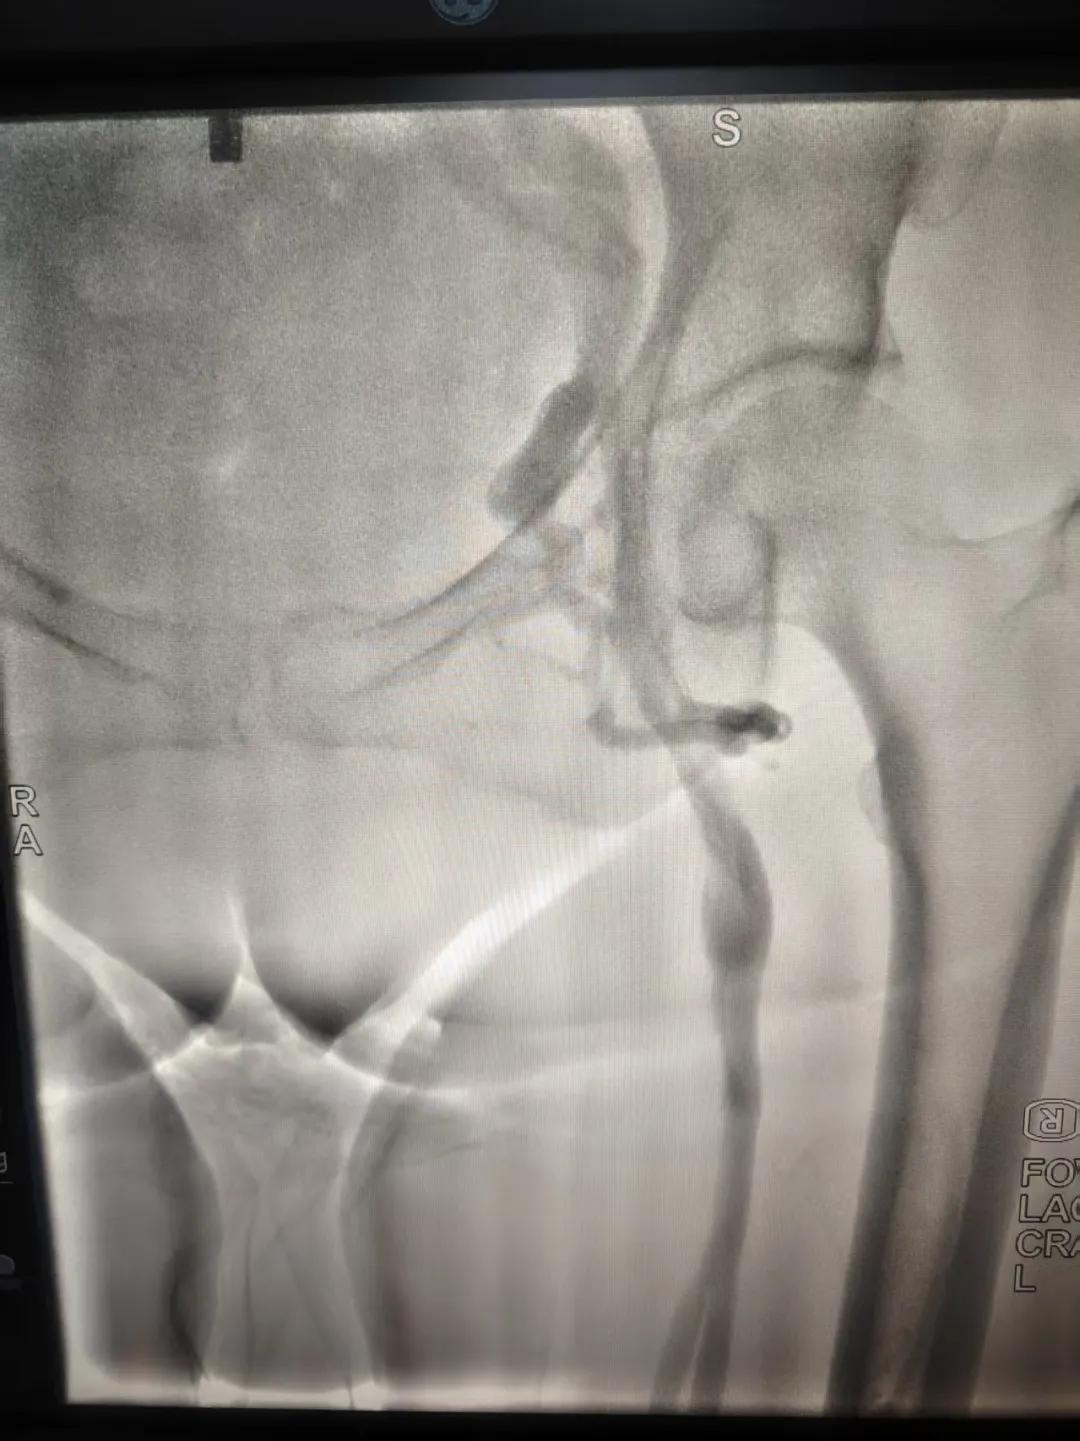

該患者,中年女性,左下肢反復(fù)腫脹、疼痛多年就醫(yī),未明病因。門診就診,經(jīng)血管外科副主任周創(chuàng)業(yè)評估病情后,為該患者門診行下肢靜脈造影,造影結(jié)果示:左髂靜脈周圍側(cè)枝形成,左髂靜脈壓迫綜合癥。明確診斷后將擇期介入手術(shù)治療。

下肢靜脈造影是診斷下肢靜脈病變(如深靜脈血栓、靜脈曲張、靜脈功能不全等)的“金標(biāo)準(zhǔn)”。靜脈造影可直觀顯示受壓部位、狹窄程度及側(cè)支循環(huán)形成情況,明確診斷與定位,指導(dǎo)治療決策,以及介入治療規(guī)劃,血栓評估,在復(fù)雜病例或介入治療中造影具有優(yōu)勢。